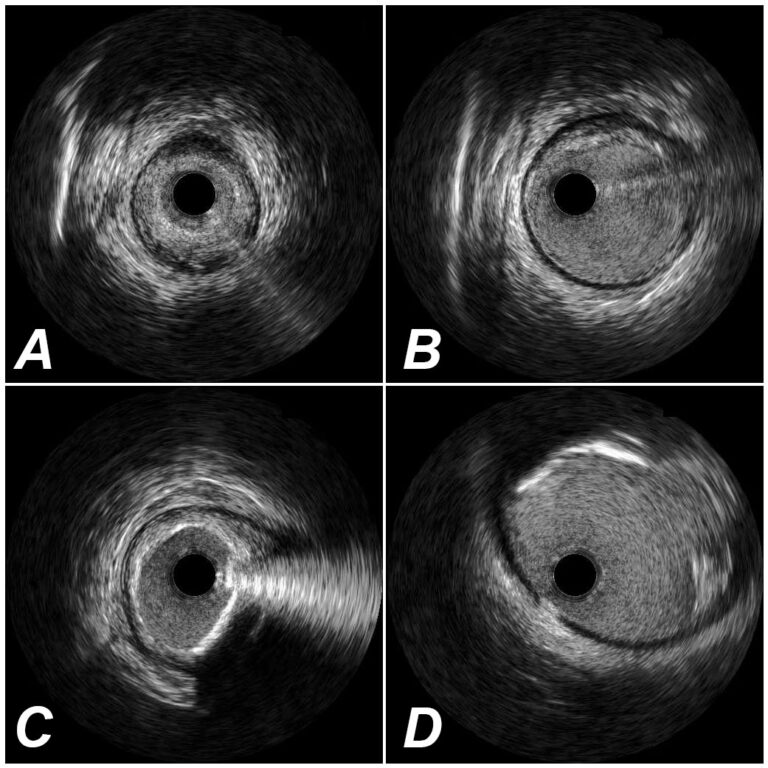

In the clinical report we describe the entire pullback: plaques, stents, minimal luminal area, particularities (like dissections, hematoma’s, thrombus, plaque ruptures) etc.

F.e: A and B show resp. concentric and eccentric fibro-fatty plaque, C shows concentric mixed plaque, fibrofatty and superficial calcium and D shows eccentric mixed plaque, fibro-fatty and superficial calcium with a plaque rupture.